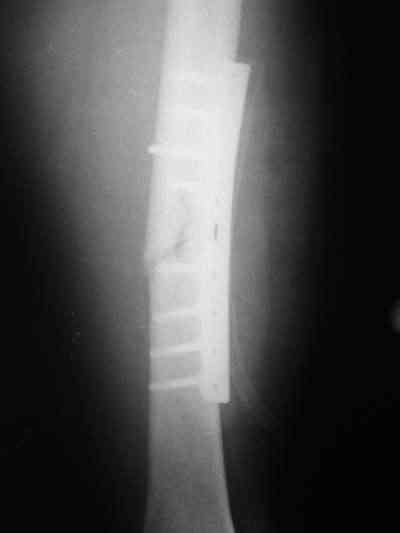

Снимки в приложении.

Конечно, при современном подходе, применение PFNa удленной версии со спиральным лезвием было бы адекватным решением. А также еще далеко до малоинвазивной техники, представленной А.Ю.Семенистым в издании Margo Anterior (МАТИС и AO/ASIF), где выполняется имплантация DHS через 4 сантиметровый разрез, снимаю шляпу перед этими мастерами, просто - высший класс, но ... какие наши годы!! ;-)

В приложении и имеющийся в наличии брейс. Приношу извинения за низкое качество снимков.